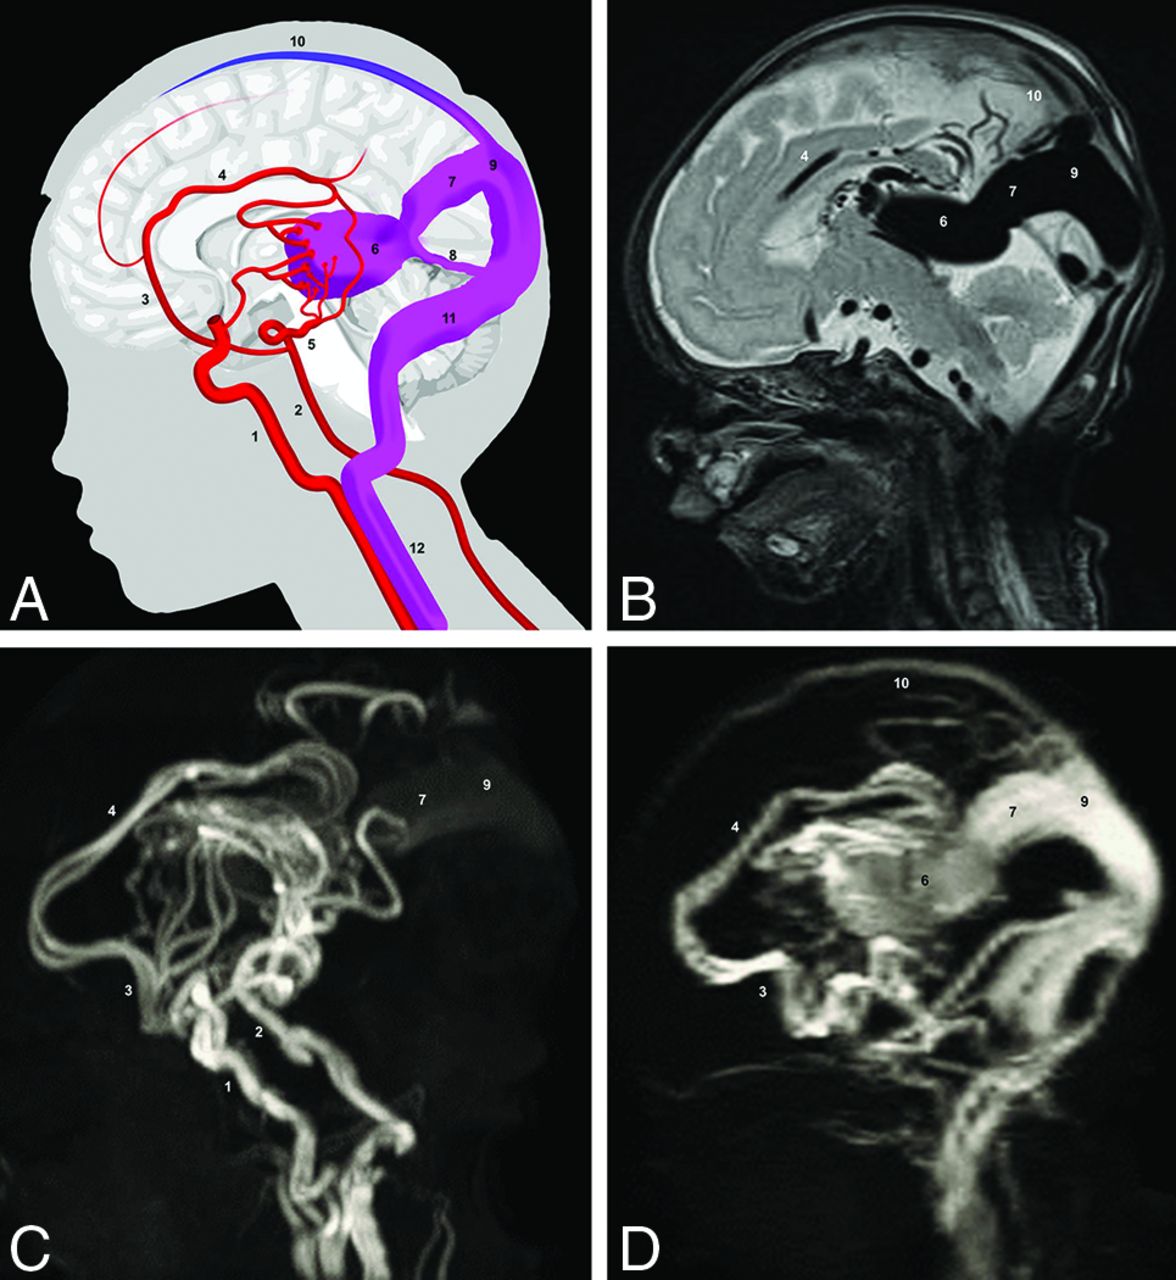

Scheme and MR imaging of a VGAM. A, Simplified scheme of VGAM. B, Sagittal T2-weighted MR image. C, Arterial TOF-MRA. D, Venous TOF-MRA. 1) internal carotid artery; 2) basilar artery; 3) anterior cerebral artery; 4) pericallosal artery; 5) posterior cerebral artery; 6) dilated MPV; 7) falcine sinus; 8) straight sinus; 9) accessory confluence; 10) SSS; 11) transverse sinus; 12) internal jugular vein.